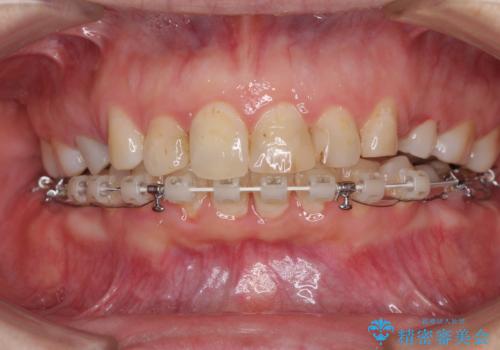

- 前歯のデコボコと前方に斜めに飛び出した前歯を気にして来院された患者様です。

口元の突出感はあまり気になっていませんでしたが、上下の前歯の前後差が大きかったため、上顎左右の第一小臼歯を抜歯し、上顎が裏側装置であるハーフリンガルにて矯正治療を行うこととしました。

咬合力が非常に強く、スペースがなかなか閉じなかったことと、上下の正中が著しくずれてきてしまったため、下顎左側小臼歯を途中抜歯することとなりました。

歯の動きが鈍く、矯正治療だけで4年以上の期間を要することとなりました。

矯正治療後は、気になっていた銀歯を全てセラミックとし、きれいな口元に仕上げることができました。